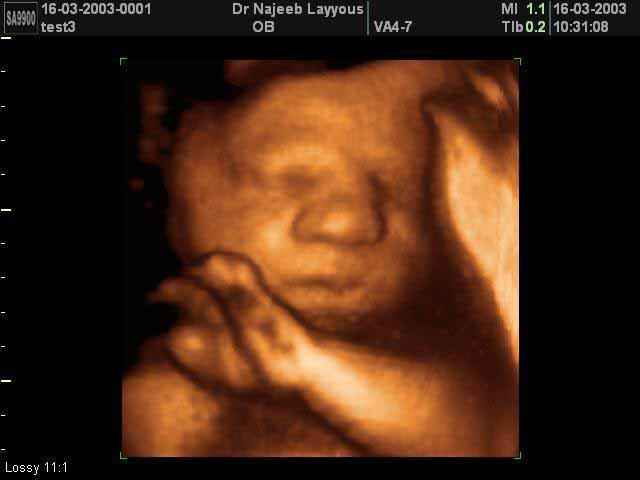

- صور لوجه الجنين في داخل الرحم

صور لوجه الجنين بجهاز الالتراساوند ثلاثي الأبعاد | الدكتور نجيب ليوس